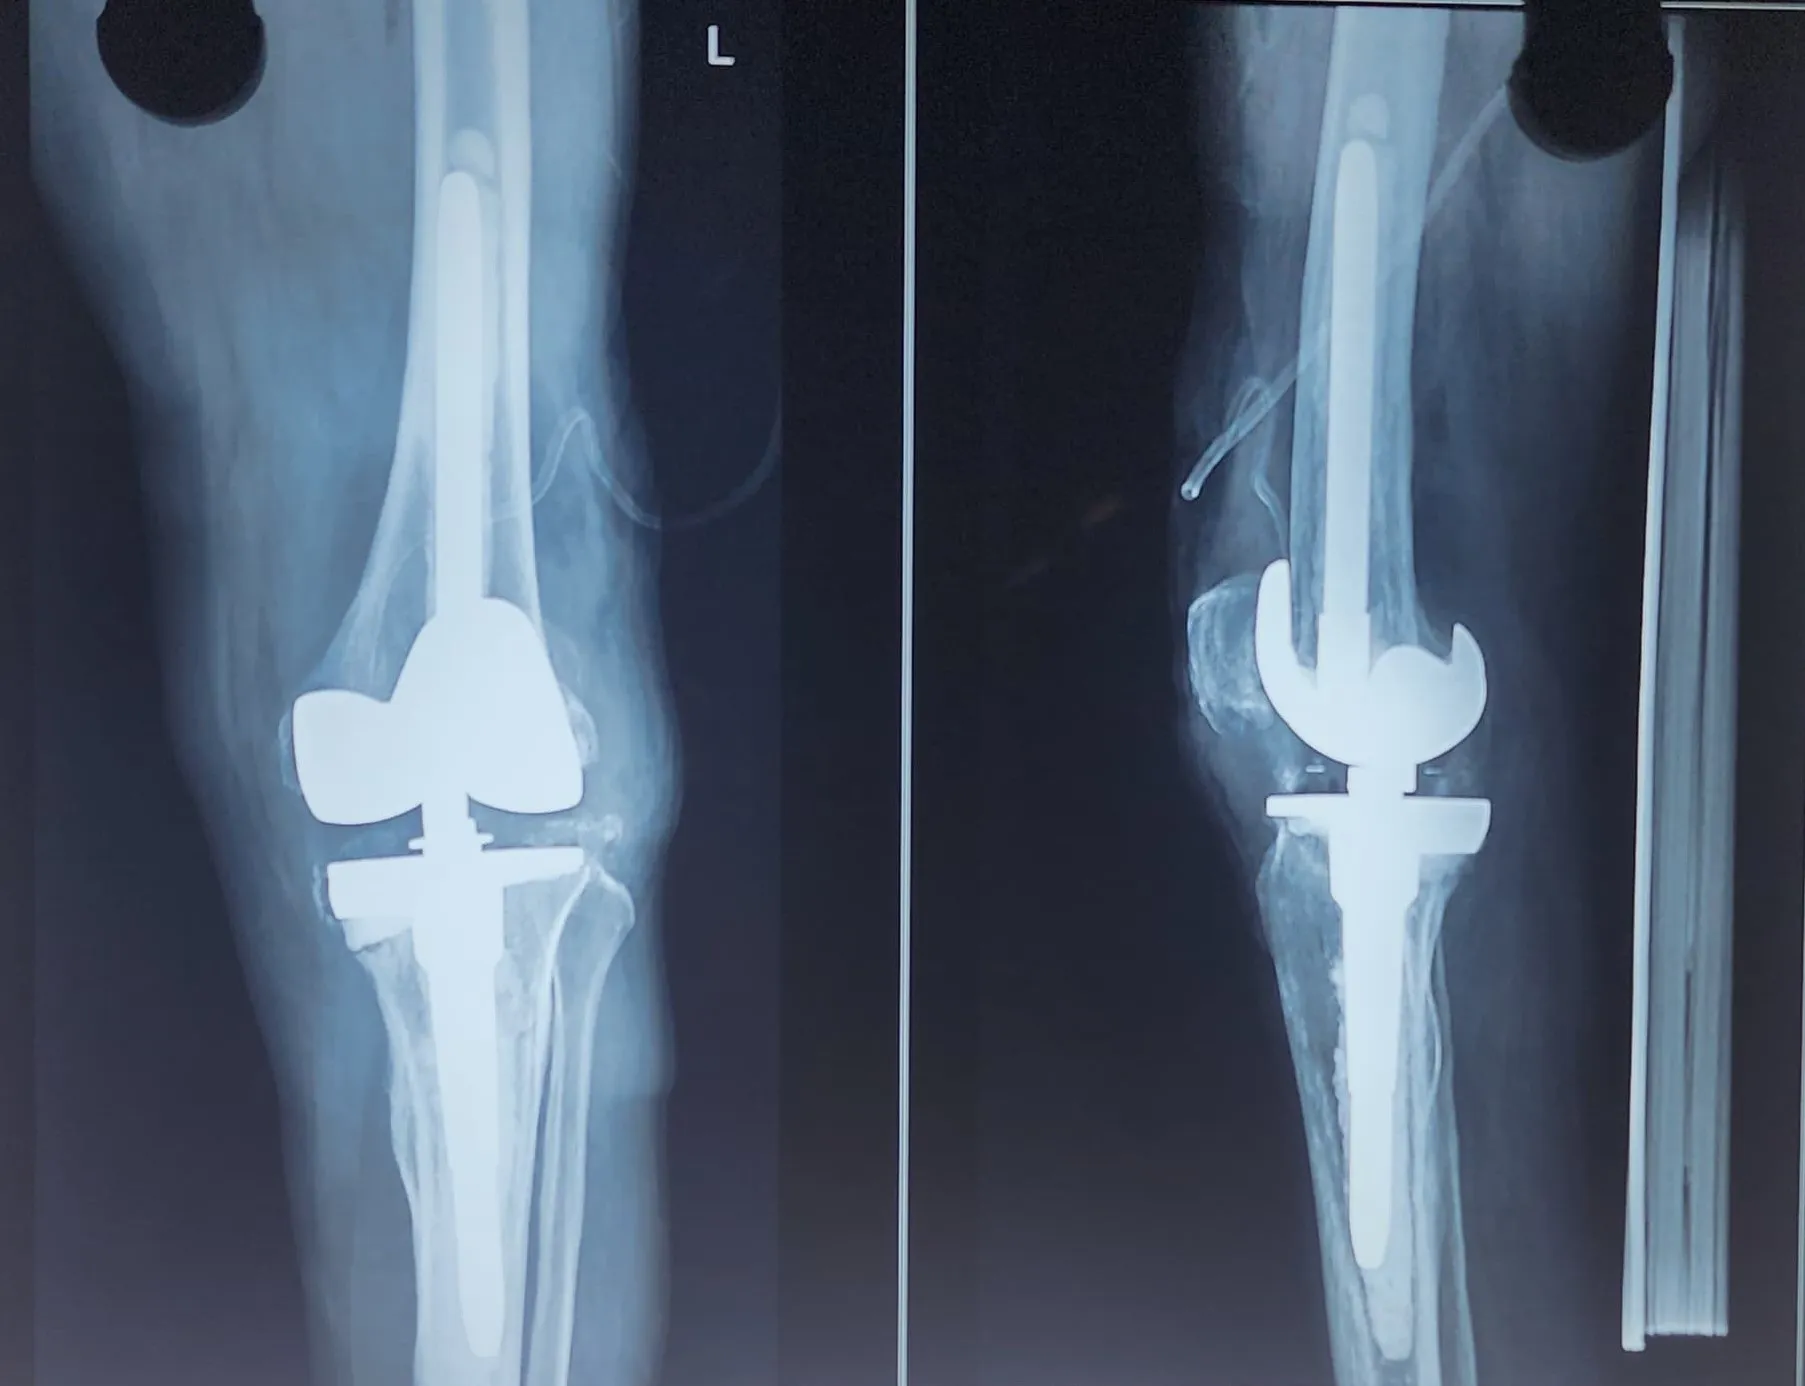

Quality and affordable healthcare has long been the essence in the field of medical sciences & treatment. Every patient expects an early diagnosis and a planned approach to treatment procedures with affordability and access to quality healthcare. Knee replacement, Hip replacement, Fracture treatment are being done by Dr.P.Sankaralingam at very affordable costs without compromising on quality.

Dr.P.Sankaralingam M.S(ortho)., DNB (ortho).,MNAMS is an experienced senior consultant Orthopaedic surgeon who does about 350 joint replacement surgeries per year in addition to treatment of Trauma cases.

Standard Hospital, Chennai’s Centre of Excellence for Orthopaedics offers minimally invasive surgeries for faster recovery.